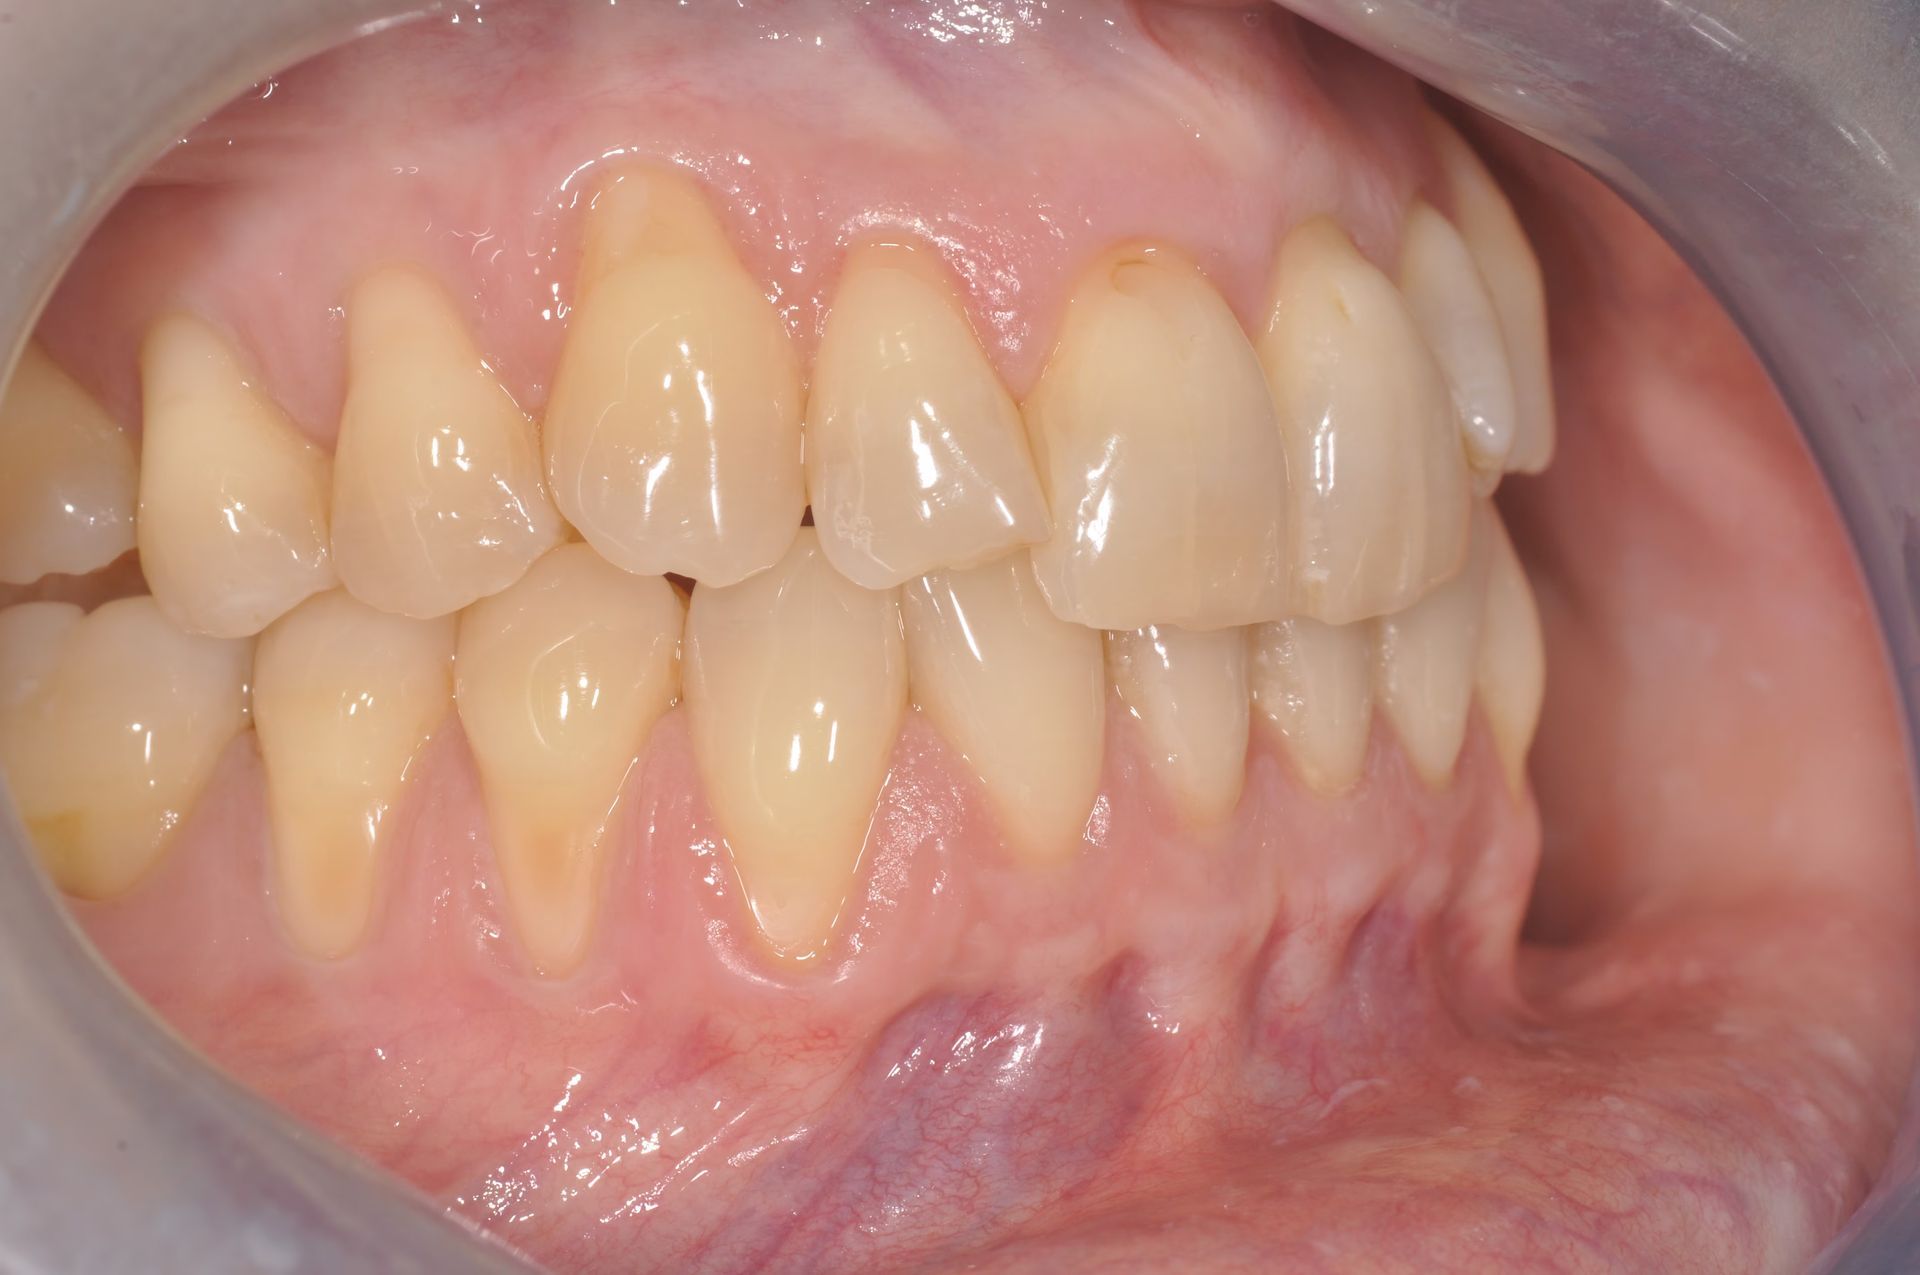

La chirurgia muco gengivale include i trattamenti dedicati alla correzione di recessioni, difetti gengivali e alterazioni estetiche del sorriso. Richiedono una tecnica che funziona nelle mani di pochi, per questo il nostro centro si avvale di uno specialista di fama internazionale, per risultati naturali, che garantiscano il successo atteso e, soprattutto, siano stabili nel tempo.

Tutti gli interventi di chirurgia orale vengono eseguiti in una sala chirurgica dedicata, in presenza di un medico anestesista, con possibilità di ricorrere alla sedazione cosciente, una procedura anestesiologica sicura e controllata che permette al paziente di entrare in uno stato di profondo rilassamento, pur rimanendo sveglio e collaborante, riducendo ansia e stress e garantendo serenità e comfort al paziente durante tutta la procedura.